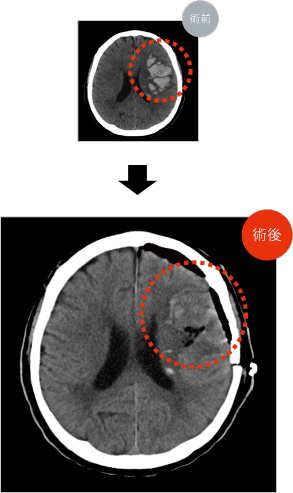

脳出血による症状は出血部位によって手足の麻痺やしびれ、意識障害など様々です。症状の強さも出血の部位、大きさにより異なります。

一般的には安静にして血圧をしっかり下げる、といった内科的な治療が中心です。しかし、血腫が大きくなると正常な脳を強く圧迫する事から、脳ヘルニアという命に関わる緊急の状態となります。ある一定以上の大型の脳内血種がある場合、意識状態などの神経症状が極めて悪い場合、命を救う目的で緊急で外科的な治療(血腫除去手術)が必要となる事があります。脳卒中ガイドラインに基づき、血腫の大きさ、部位、年齢、神経所見、全身状態などを考慮して決定しております。

他方、近年の内視鏡を用いた医療の進歩は目覚ましいです。脳神経外科の領域でも、手術や機器が飛躍的に発展・普及してきています。これに伴い、脳出血に対する、より低侵襲かつ安全な治療方法としての神経内視鏡手術が、広く行われる事が可能となってきました。開頭手術、神経内視鏡手術のいずれも行う事ができる当科においては、対応可能な場合は、より低侵襲な神経内視鏡手術を現在積極的に行っています。